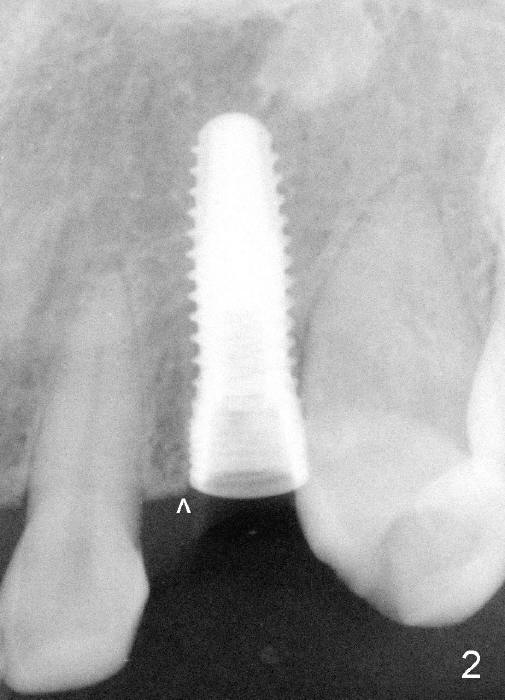

The 42-year-old lady refuses to take antibiotic prior to surgery due to lactation. The extraction of the upper left deciduous canine is not difficult as expected. There appears to be no granulation tissue. What is unexpected is difficulty in osteotomy. Initial osteotomy is too palatal, apparently perforating the palatal plate. The osteotomy has to be changed: slightly palatal to the center of the original socket (Fig.1: 2 mm pilot drill). As drills increase in diameter, the coronal end of the drills have to be tilted buccally, because it feels like that the labial plate at the apical end is going to be perforated. When 4.5x14 mm bone level implant is placed, the implant is sticking out too much (Fig.2). To alleviate this cosmetic issue, the implant is placed deeper (Fig.3). A 25º angled abutment is placed with heavy labial reduction (Fig.4,5). The patient is pleased with a stable new tooth, but the operator is not (Fig.6). Removal of the implant may be not the wildest guess. Two or three days postop, the patient reports pain and swelling. The symptoms disappears after antibiotic. One week follow up reveals wound healing normal. The gingiva returns to its normal color, as compared to purplish appearance in Fig.4,6 (immediately postop). In fact, the implant fails in a month.